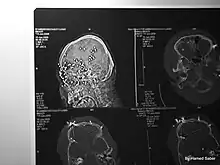

X-ray of an Iranian protestor who suffered eye damage after being shot in the face with a non-lethal stinger round in 2009

Kinetic-impact-projectiles (KIPs) also known as baton rounds, or rubber/plastic bullets are non-lethal projectiles used for crowd control purposes by riot police.[6][7][8] KIPs are marketed as non or less-lethal weapons used for the purposes of dispersing crowds without causing penetrating wounds.[6] However, when used inappropriately and fired indiscriminately, they have been known to cause injuries leading to life-long disability, or even death.[6][7][9] Examples of KIPs include rubber or plastic bullets, bean bag rounds, sponge rounds (rounds with a softer nose/tip to limit impact) or pellet rounds of birdshot or buckshot.[6][7] Hosein Jafari, 28 at the time, was attending a protest in Tehran with Farzi when he was shot in the back of the head with a pellet gun.[10] Medical imaging scans shared on his Instagram page show 6 of the 8 pellets that entered his body remain, one in his neck and the rest in his head.[10] Abolfazl Adinezadeh, a 17 year old boy that had joined the Woman, Life, Freedom protests is one of many examples of protesters in Iran who have been killed as a result of close range discharge of KIPs.[9][11] Cases have also been reported in which protesters have either been killed, or lost an eye as a result of being hit directly by tear gas canisters.[7][12][13][14] Abolfazl Amirataie, a 16 year old boy who had joined protests on 22 September 2022 was shot directly in the head at close range with a tear gas canister, causing catastrophic damage to one side of his skull and brain.[15] After 8 months in a vegetative state, Amirataie succumbed to his injuries on 27 May 2023.[15]